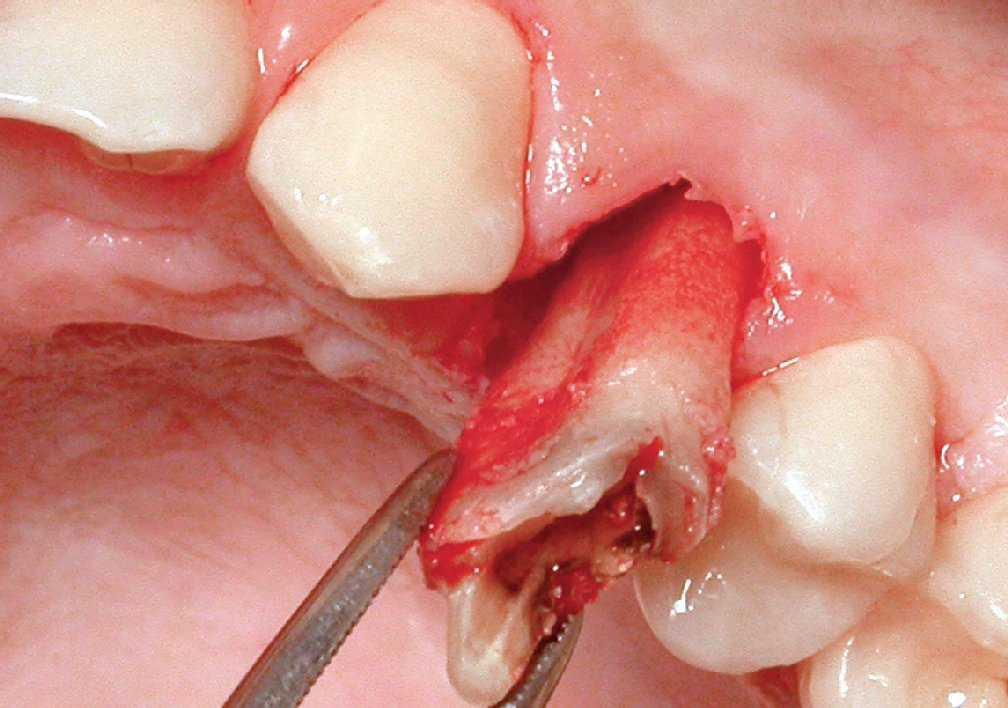

La extracción se efectuó usando las puntas del equipo de extracción (figura 1). La punta en forma de flecha se introdujo en el surco a una profundidad de 4-5 mm sin separar primero la encía del diente, alrededor de toda la circunferencia de éste. No se evidenció hemorragia mientras se progresaba en dirección apical (figuras 3a y 3b). Acto seguido, se usaron sindesmotomos rectos o angulados para cortar en profundidad las fibras del LPD (hasta 10 mm o más). Tras la sección de las fibras del ligamento, el diente se movilizó con un sindesmotomo de Claude Bernard (figura 3c) y se extrajo del alveolo con unas pinzas (figura 3d). En el caso de dientes anquilosados, se usaron sindesmotomos de vibración para desprender la raíz del hueso fijado circundante.

Figura 3c Para levantar el premolar se usó un elevador (sindesmotomo de Claude Bernard).

Figura 3d El diente se extrajo de una pieza con pinzas tras la elevación con un sindesmotomo manual.

La extracción se efectuó con un corte de las fibras del LPD antes de la movilización del diente. Los dientes o raíces frágiles tratados con endodoncia (n = 28), que, de otro modo, se habrían fracturado, se extrajeron en una pieza sin fractura. El diente anquilosado también se extrajo de una pieza sin necesidad de cirugía invasiva.

Durante la extracción, la hemorragia fue limitada. Esto no resultó sorprendente, ya que Blus y Szmukler-Moncler13 describieron previamente que el corte de la encía con una punta similar no provoca hemorragia, como consecuencia de la oclusión temporal de los capilares. Este método de extracción es particularmente pertinente y atraumático cuando los dientes o raíces cariados son demasiado frágiles para extraerlos sin fracturarlos en varios segmentos pequeños. Se efectúa un corte de las fibras de LPD con la punta de tipo flecha y el sindesmotomo; acto seguido, es posible levantar el diente o la raíz débil sin su lesión. Un diente anquilosado también puede separarse de una pieza del hueso al que se une. Por lo tanto, pueden evitarse los procedimientos quirúrgicos invasivos que más tarde requieren injertos óseos y de tejido blando antes de la colocación del implante4,21.